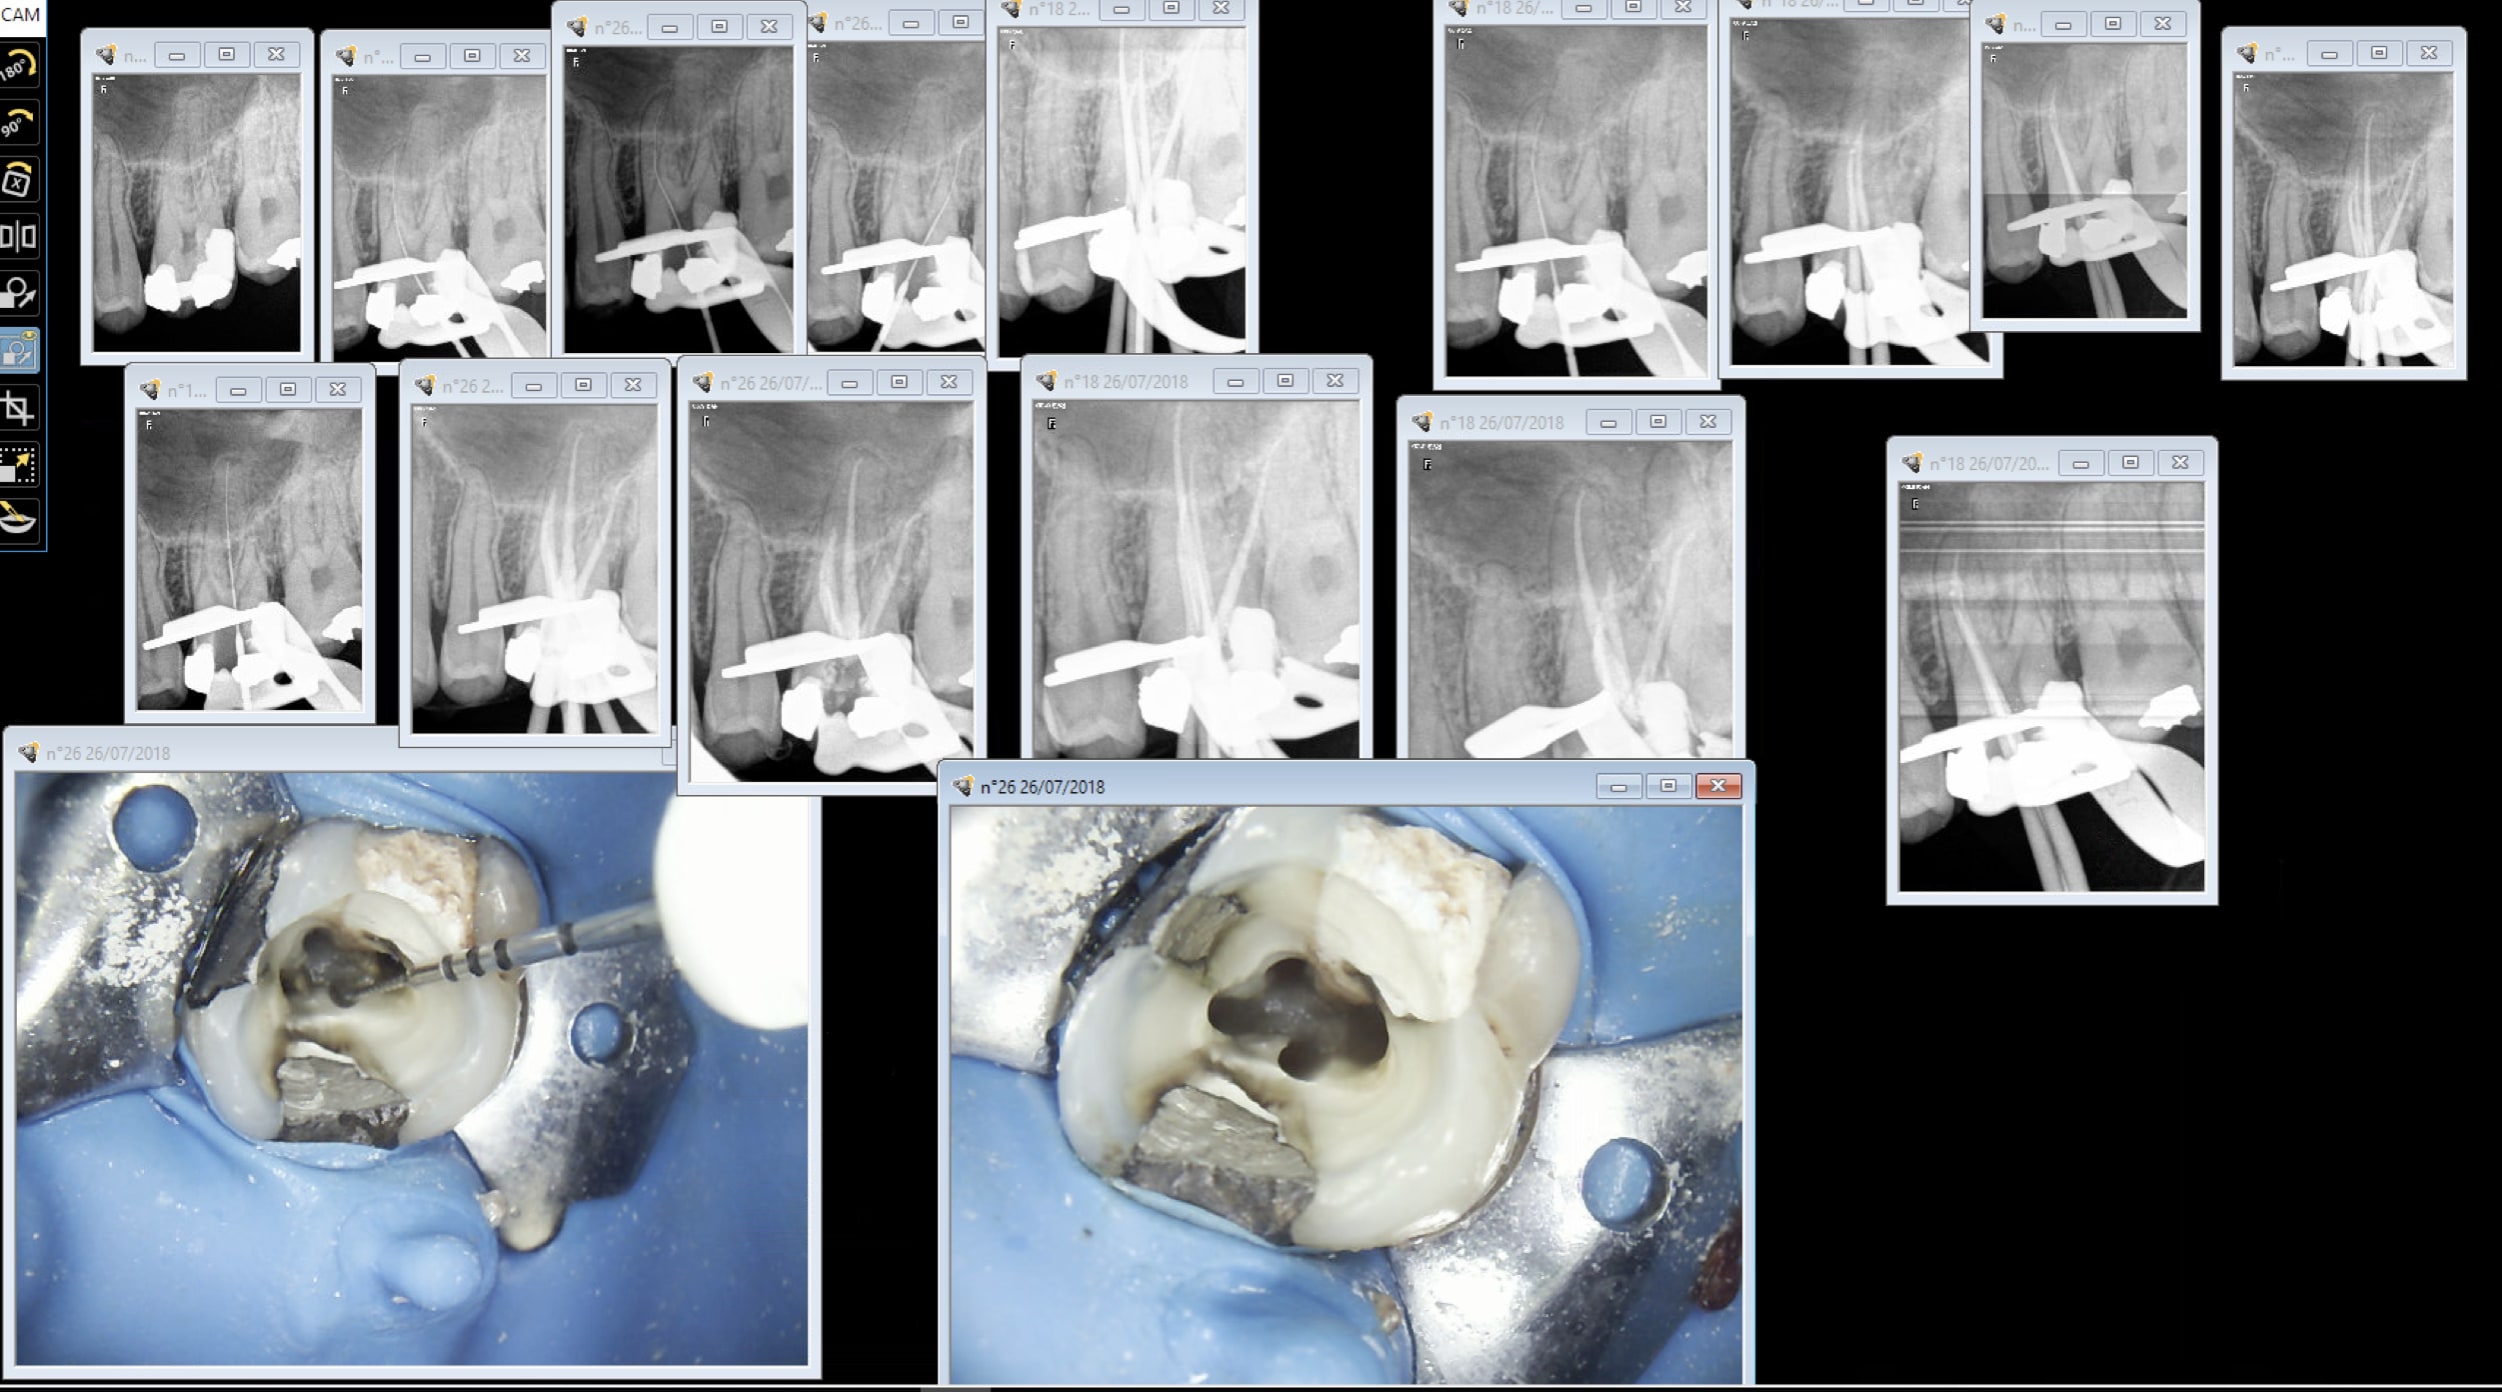

OK une autre plaque faut jouer avec les filtres avec le capteur non. Ca se ruine assez vite les plaques et ça vaut la peau du derche. Excuses moi le capteur est plus vieux de 5 ans que ces plaques de merde.

Capture d écran 2018 07 25 20.21 - Eugenol

C'est un constat plaques vieilles ou pas plus de boulot à tirer un cliché valable ( gestion du temps d'expo par ex, faire gaffe à ce qu'elles ne prennent pas la lumière au développement ensacheter dés-ensacheter). Le capteur c'est 0,09 s de temps d'exposition point barre. J'ai les 2 bordel pour moi il n'y a pas photo. Faut pas acheter des capteurs de merde non plus. Quand t'en fais 2 dans ta journée tu peux t'appliquer mais quand t'en fais 50 ca commence à etre casses burnes. -)))

Amusez vous bien avec vos plaques. -)))

Capture d écran 2018 07 27 00.23 - Eugenol